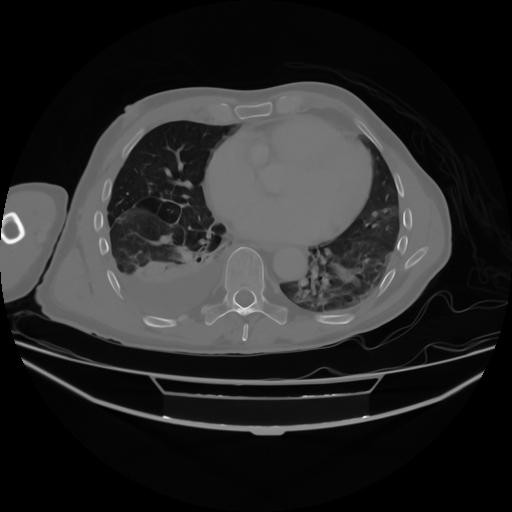

4 CUERPO,CE,Axial,3.0,CUERPO,,